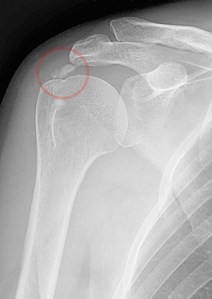

And how did I arrive at this horrifying conclusion? Well, I recently had an upper chest X-ray as a precursor to the MRI, and on Thursday, I was able to access the report through the radiology clinic dashboard. It was pretty humdrum, and I was getting more than a little miffed once again at the liberal use of the term “unremarkable” (although I was pleased to note that my lungs are apparently “well-aerated”) when it said this: Cholecystectomy clips noted. I was like “What the f*ck is a chole-thingy?” so I googled it, and it’s when you have your gall bladder removed, and I did that about 20 years ago. I realize I’ve just made it sound like I reached into my own abdominal cavity and pulled it out myself, and if that did indeed happen, you will note that I would have accompanied the pulling out of my gall bladder with a flourish and the words Abracadabra, but a surgeon did it, and he was a terrible magician. And I KNOW this because in the same way that a terrible magician would accidentally sit on the top hat and kill his rabbit, this person left METAL CLIPS inside my body. I’ve been setting off the airport security alarms for years and telling them it was MY BELT when, in fact, I am a human IED.